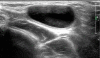

The processus vaginalis within the inguinal canal forms the canal of Nuck, which is a homolog of the processus vaginalis in women. Incomplete obliteration of the processus vaginalis causes indirect inguinal hernia or hydrocele of the canal of Nuck, a very rare condition in women. Here, we report 2 cases of hydrocele of the canal of Nuck that were diagnosed with ultrasonography in both cases and magnetic resonance imaging in 1 case to confirm the sonographic diagnosis. High ligation and hydrocelectomy were conducted in both patients. In 1 patient, 14 months later, the occurrence of contralateral inguinal hernia was suspected, but did not require surgery. The other patient had a history of surgery for left inguinal hernia 11 months before the occurrence of right hydrocele of the canal of Nuck. In both cases, the occurrence of an inguinal hernia on the contralateral side was noted.